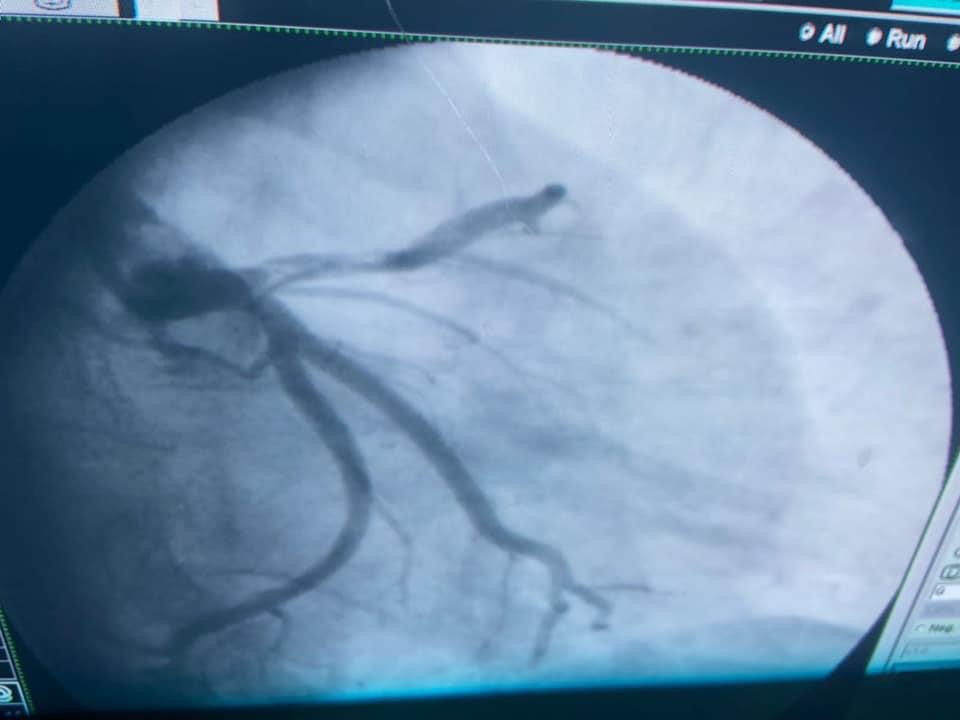

من ناحيته، أوضح الدكتور شرف الدين شاذلي، رئيس وحدة قسطرة القلب بالمستشفى الجامعي، أن فريق العمل بجراحة الأوعية الدموية قام بعمل سحب وإذابة جلطة الساق، وبعدها تدخل أطباء وحدة القسطرة لعمل قسطرة عاجلة للقلب لسحب الجلطة وتركيب دعامة الشريان التاجي عن طريق الذراع، وبفضل الله وعنايته، المريض الآن بحالة جيدة ويتماثل حالياً للشفاء في عناية القلب بالمستشفى الجامعي.